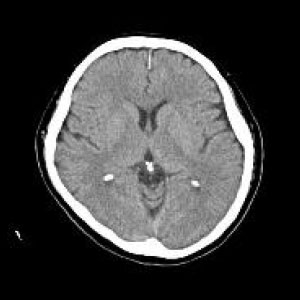

CTとはComputed Tomography(コンピュータ断層撮影)の略です。

検査はエックス線を利用し体の断面を撮影します。頭から全身に至るまで様々な検査が可能です。当院では80列マルチスライスCTを導入し短時間で低被ばくかつ高精細な検査が可能となりました。

脳血管障害、脳腫瘍、頭部外傷、顔面骨骨折、副鼻腔炎、甲状腺疾患、肺炎、肺がん、食道がん、肺塞栓、縦隔疾患、消化管疾患・がん・炎症、泌尿器疾患、婦人科疾患、大動脈瘤、脊椎骨折、骨盤骨折、上下四肢骨折、下肢動静脈疾患など